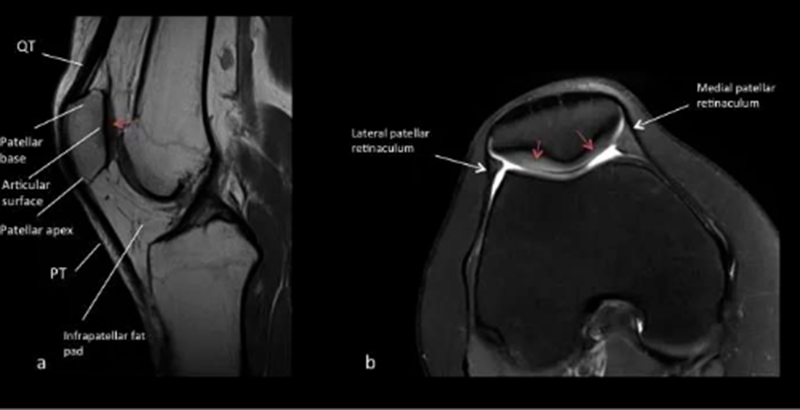

常见影像学检查包括X线、CT和MRI检查。X线早期无异常,直到晚期阶段,如出现广泛的软骨丧失、关节间隙丧失及相关的软骨下骨硬化和囊性变化,X线可诊断。MRI是非侵入性诊断方法,有望在肉眼可见的形态学软骨损失之前检测软骨病变以及软骨内部紊乱的独特功能。

正常MR a.矢状位T1W1 b.横断位T2W1